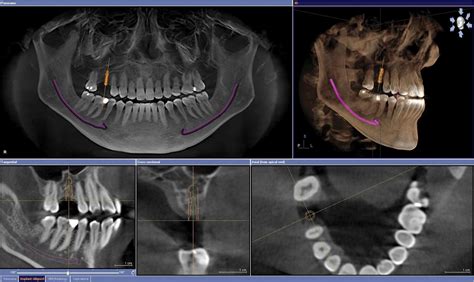

La exploración mediante tac dental o tomografía computarizada para el diagnóstico maxilofacial debe ser efectuada con equipos que dispongan de programas informáticos de reformación multiplanar (MPR). La tomografía computarizada de haz cónico (TCHC), más comunmente conocida por sus siglas inglesas (CBCT, cone beam computed tomography), que también se conoce como 3D gracias a su capacidad para generar imágenes tridimensionales, es, indudablemente, la técnica de diagnóstico por imagen con mayor proyección actualmente.

El Cone beam o CBCT (Cone Beam Computed Tomography), llamado también tomografía volumétrica digital de haz cónico, es una técnica de imagen seccional en 3D en pleno auge. Como su nombre indica, el tac dental consiste en un generador de rayos X que emite un haz de irradiación abierto de forma cónica que, en una rotación completa (360º) o semicompleta (180º), permite recorrer todo el volumen a explorar antes de analizarlo tras atenuar los rayos mediante un sistema de detección.

- Implantología: Permite estudiar la estructura ósea para determinar la posición exacta del implante dental, comprobar la dimensión ósea y evaluar la necesidad de regeneración ósea o elevación de seno maxilar.

- Cirugía Oral y Maxilofacial: Para la extracción de muelas del juicio, evaluación de patologías de las articulaciones temporomandibulares (ATM), y planificación de cirugías ortognáticas.

El desarrollo de la CBCT como técnica de diagnóstico bucofacial representa un cambio radical de la radiología dental y maxilofacial, ya que acerca la tomografía computarizada a la práctica clínica diaria. El éxito de la CBCT se debe a que ha facilitado de forma generalizada la transición de las imágenes radiográficas, en el diagnóstico odontoestomatológico, desde el 2D al 3D.